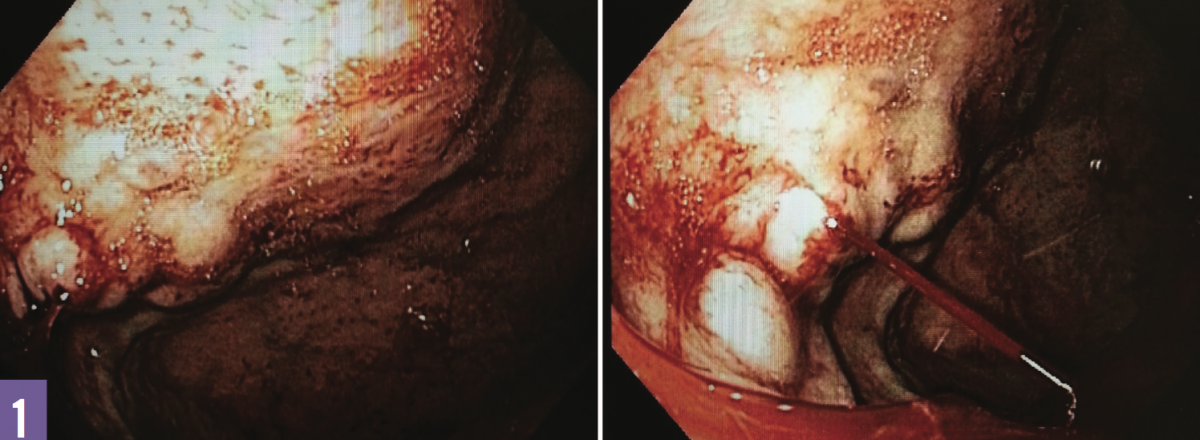

Treatment. The patient underwent an emergent esophagogastroduodenoscopy (EGD), the results of which revealed active intermittent bleeding from moderate-sized gastric varices (GVs) in the fundus (Figure 1). The GVs could not be treated endoscopically. Emergent interventional radiology evaluation was advised with transjugular intrahepatic portosystemic shunt (TIPS) placement. The patient underwent hepatic venography and pressure measurements, which revealed no portal hypertension. Thus, TIPS was not indicated owing to the absence of portal hypertension, and proceeding with splenic angiography was advised.

Figure 1: Gastric varices in the fundus (left); an actively bleeding varix (right).